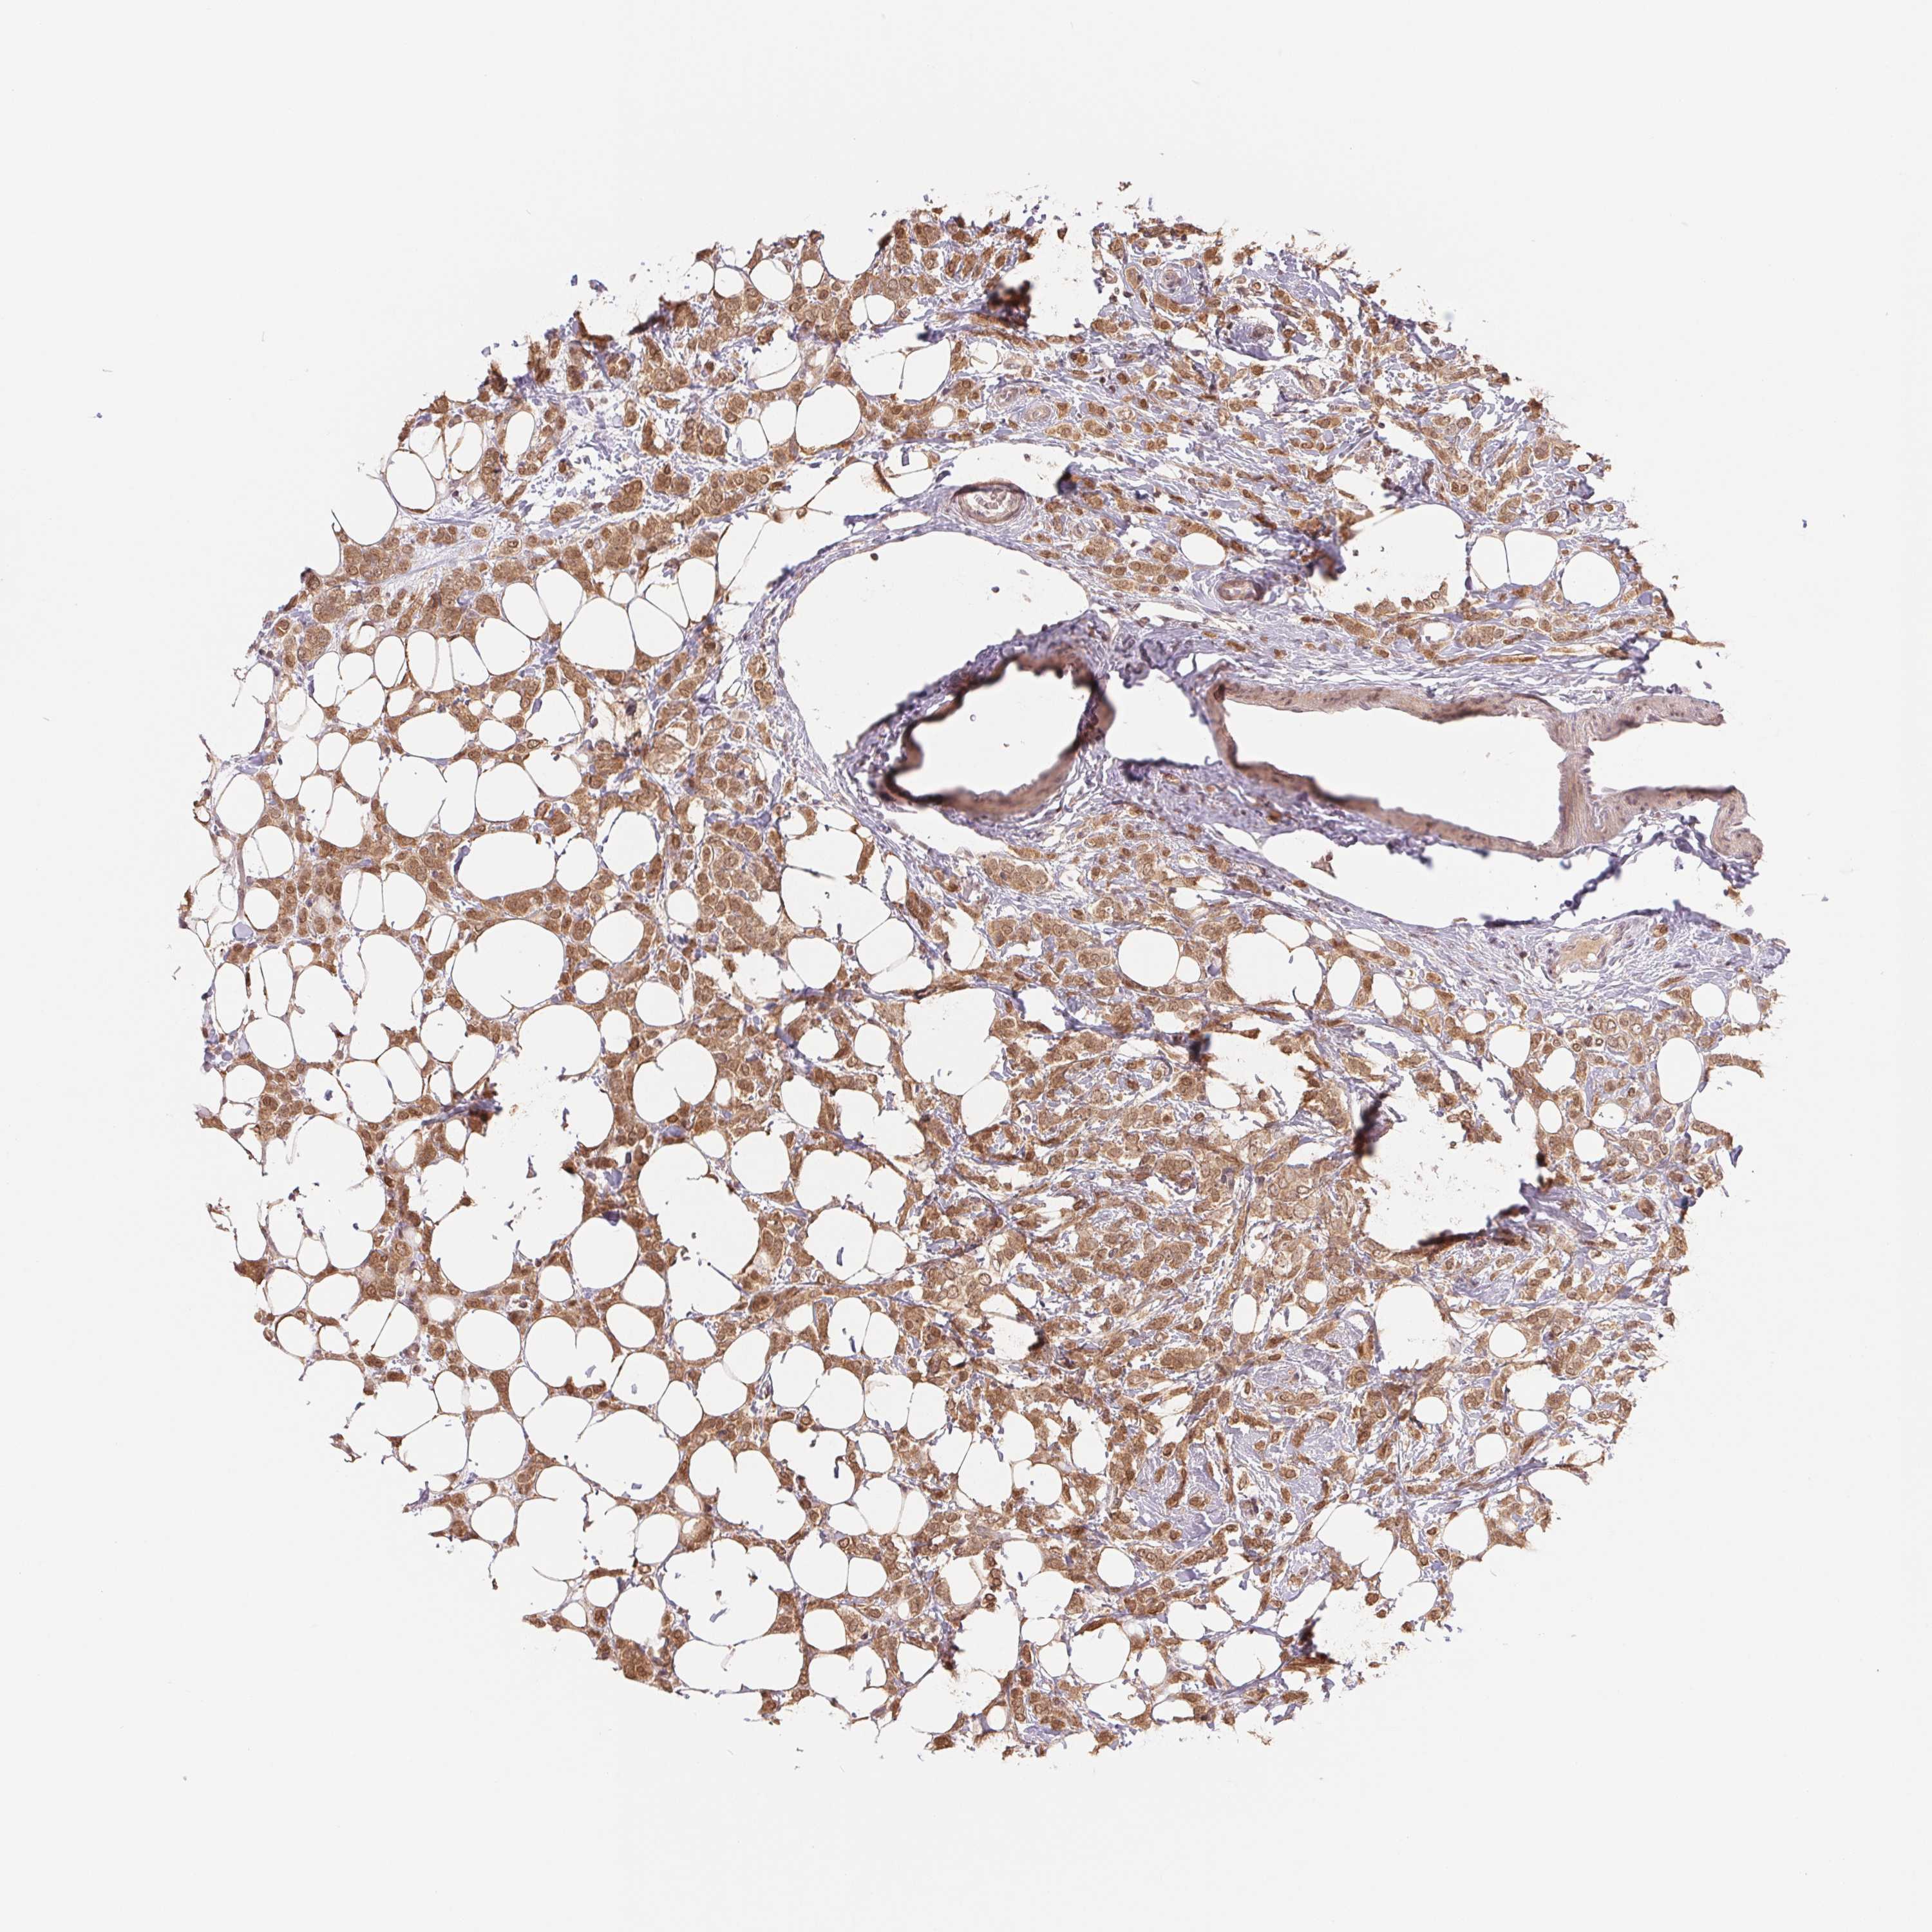

BRCA TCGA BRCA VALIDATION PROTEIN EXPRESSION

ANTIBODIES

AND

VALIDATION